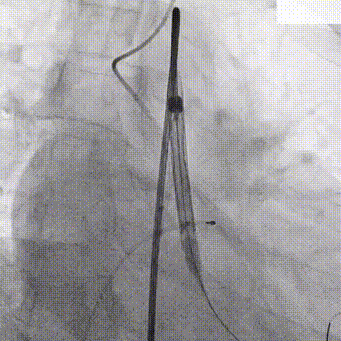

主动脉根部造影

20mm TaurusAtlas球囊

输送系统过弓

确定初始释放位

瓣膜稳定释放至工作位

TaurusOne AV23mm瓣膜瓣下3-4mm 工作位造影

瓣膜完全释放

瓣膜位置理想